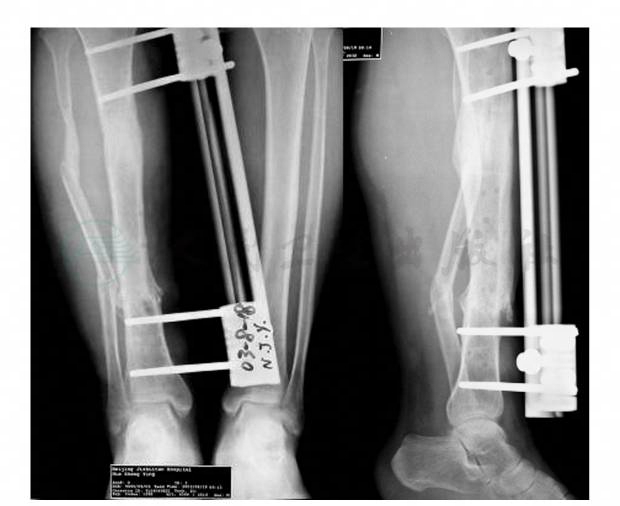

骨科专科情况:患者平卧位,左大腿无明显畸形,以单边外固定架固定。右小腿中段前内侧皮肤缺损约5cm×3cm,胫骨前内侧骨质缺如,后外侧骨质外露,伤口有脓性分泌物。周围皮肤轻度肿胀,局部皮温不高。在小腿前外侧有一个长约15cm的L形切口瘢痕。右小腿前内侧以国产单边外固定架固定胫骨(图1)。踝关节跖屈、背伸:10°~5°(主、被动一致),足部动脉搏动可及,毛细血管充盈时间正常,足趾活动正常。左膝关节屈伸:15°~0° (主、被动一致)。X线片示:左股骨骨折,外固定架固定,骨折对位、对线良好。右胫骨远段粉碎骨折,骨折对位、对线好,前内侧有部分骨质缺损,胫骨以外固定架固定;腓骨中下1/3交界处短斜行骨折,骨折远端向外移位约1个皮质(图2)。

图2 术前X线片